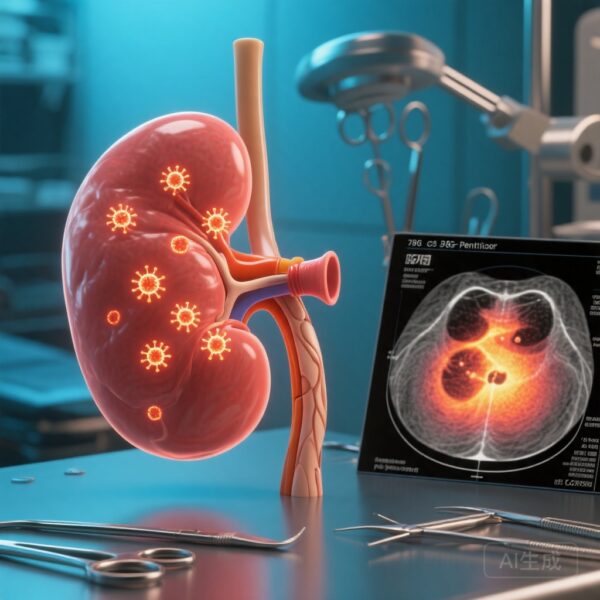

手術管理への影響

MIは、抗逆流手術に最も利益があると考えられる患者を特定するための客観的基準を提供します。異なるGERD型を区別することで、手術アプローチをカスタマイズし、症状解決の現実的な期待値を設定することができます。術後、MIは粘膜回復と手術成功を評価するバイオマーカーとして機能します。